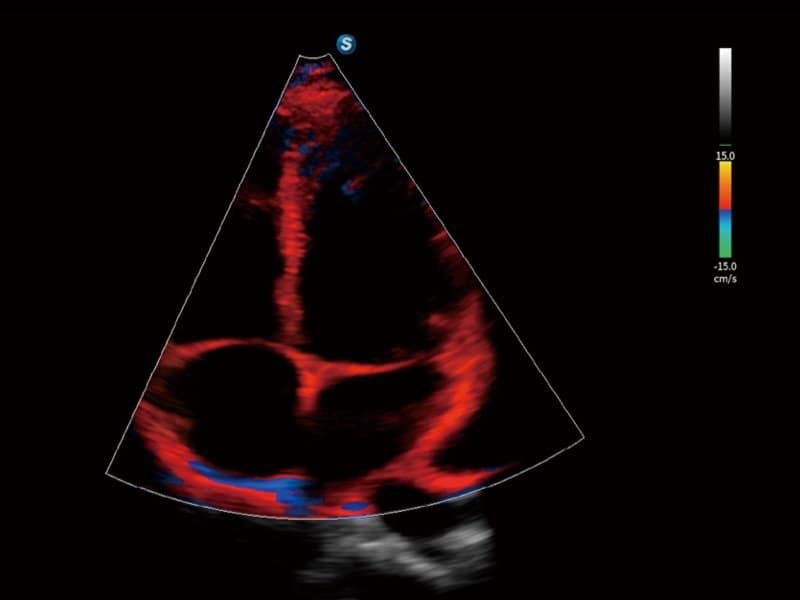

Klinische Bilder

- Kardiologie: Automatische Identifizierung von Herzstrukturen via S-CV (TDI/Messung), Stress-Echokardiographie und MQA zur Bewegungsanalyse.